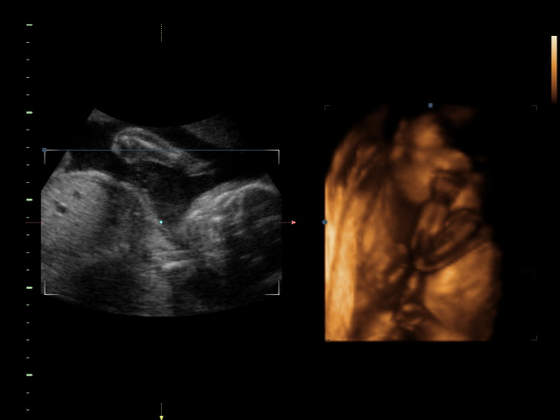

Cyntia wszystko w porzadku i glowka Mai podniesiona i nie uciska tam gdzie nie trzeba. :-)